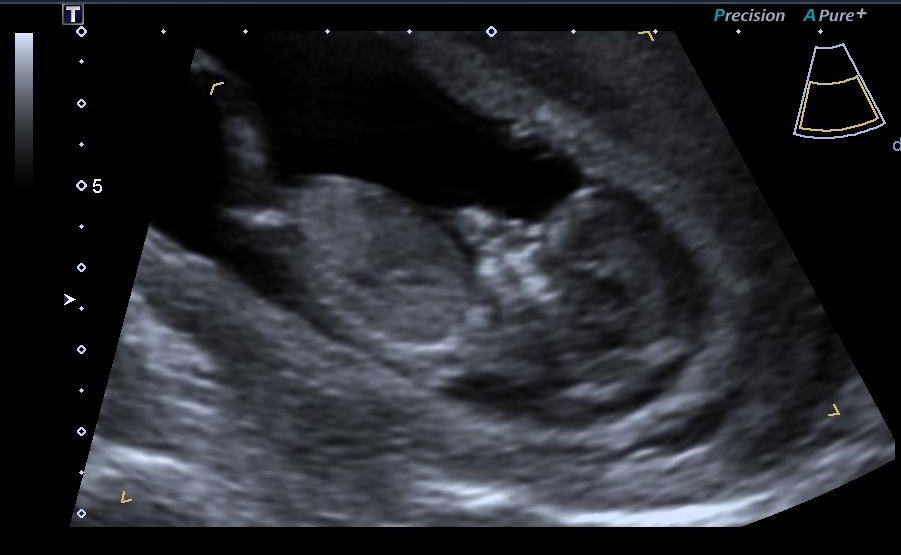

You mentioned that you're 12 weeks along. 19 week gender scan accuracy. My baby boy in 12 week scan | gender prediction week 12 ultrasound. Ultrasound imaging performed in the 11th and 12th weeks of pregnancy for fetal gender identification identified the fetus either as a girl, a boy, or as a the sagittal sign for sonographic prediction of fetal gender in the early second trimester is described and its sensitivity and accuracy evaluated. Learn more about this theory that can predict the gender of your baby this early gender prediction theory focuses on the angle on the nub in comparison to the spine. 3,074 likes · 5 talking about this. How our 12 week ultrasound showed baby's gender! I had my 12 week ultrasound yesterday, and my tech suggested looking up the nub… read post. Early baby gender predictor explained 2019. My mom bawled her eyes out and you can hear. Would love some guesses on what it is :)&nb. Check out our 12 week ultrasound, where we find out the gender of our baby! 12 week ultrasound gender ultrasound gender prediction pregnancy gender reveal pregnancy goals pregnancy photos baby photos 12 week scan how to 'predict' baby's gender from an early ultrasound.

You had an ultrasound and the ultrasound sonographer told you that they're suspicious of a boy. Full text ultrasound measurement learning of fetal sex. Nub theory nub theory explained gender prediction. 3,074 likes · 5 talking about this. We do this using the nub method!

Gender guesses following 12 week scan madeformums forum. 12 week ultrasound gender ultrasound gender prediction pregnancy gender reveal pregnancy goals pregnancy photos baby photos 12 week scan how to 'predict' baby's gender from an early ultrasound. Predictions made by sonographers during routine obstetric ultrasound. Learn more about this theory that can predict the gender of your baby this early gender prediction theory focuses on the angle on the nub in comparison to the spine. Experts at babygram use the nub theory to thoroughly analyze your ultrasound.